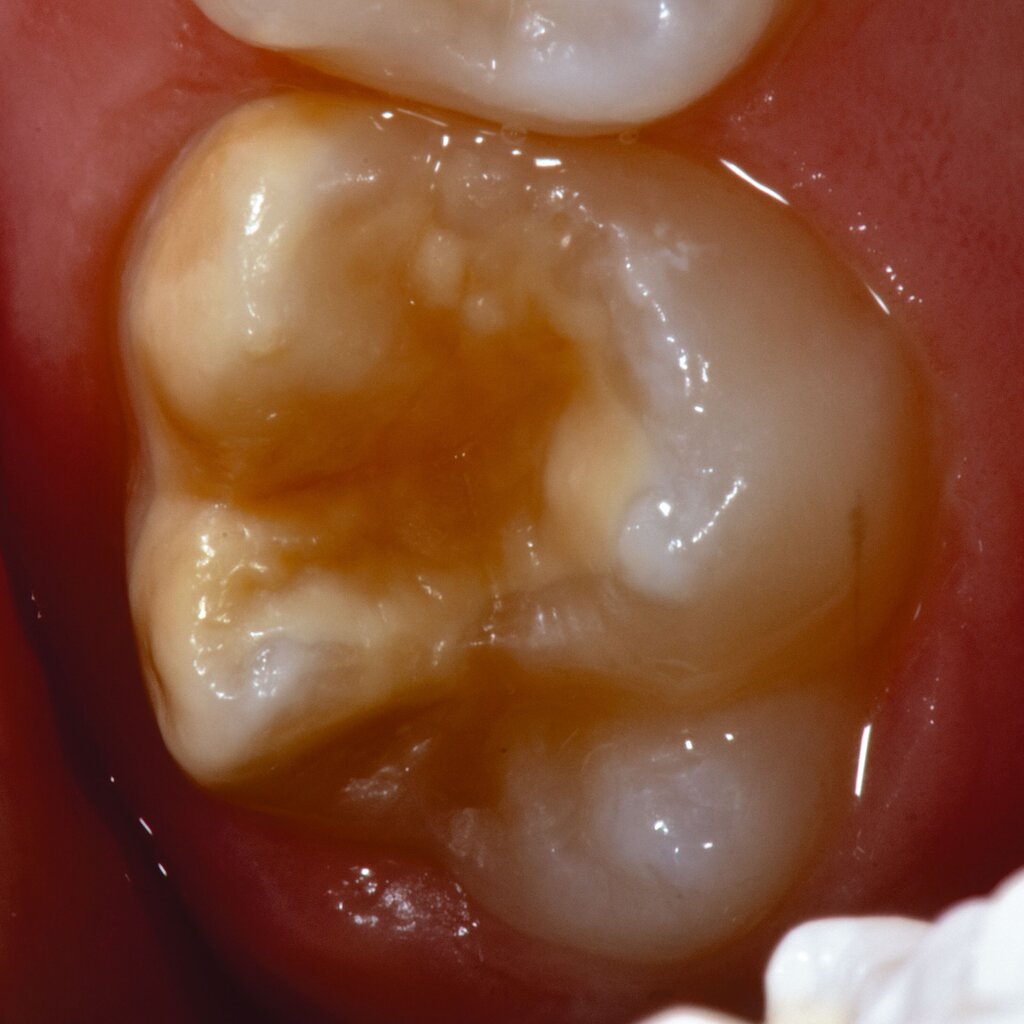

An umfangreich hypomineralisierten Zähnen können Schmelzeinbrüche (engl.: „enamel breakdown“ oder „enamel desintegration“, Abbildung 5) auftreten [Lygidakis et al., 2010; 2022]. Da diese oftmals die Folge einer fehlenden Belastungsfähigkeit des Zahnschmelzes sind und erst nach der Einstellung der Zähne in die Okklusion auftreten, werden sie auch als posteruptive Schmelzeinbrüche bezeichnet. Sie sind häufig im Bereich der Kauflächen beziehungsweise Höcker der Molaren zu finden, führen zur Dentinexposition und damit einhergehend zu ausgeprägten Hypersensitiven insbesondere bei Kindern, deren Zähne gerade erst durchgebrochen sind [Linner et al., 2021].

Bei post- beziehungsweise präeruptiven Oberflächendefekten ergibt sich in einigen Fällen die Indikation zur Restauration dieser MIH-Zähne. Unter Verweis auf die Lokalisation von MIH-bedingten Hypomineralisationen außerhalb der typischen Kariesprädilektionsstellen – zum Beispiel okklusale Fissuren und Grübchen oder Approximalflächen – werden diese als „atypische Restaurationen“ (engl.: „atypical restoration“, Abbildung 6) klassifiziert. Als ein weiteres Erkennungsmerkmal gilt die Präsenz von Hypomineralisationen im Bereich der Restaurationsränder. MIH- und kariesbedingte Restaurationen können und sollten sicher voneinander abgegrenzt werden.

Für die Dokumentation und Klassifikation der MIH wurden verschiedene Systeme vorgeschlagen. Als historisch und veraltet gilt der (modifizierte) DDE-Index. Demgegenüber haben die Kriterien der EAPD – abgegrenzte Opazitäten (Abbildung 3 und 4), Schmelzeinbrüche (Abbildung 5), atypische Restaurationen (Abbildung 6) – mittlerweile die weiteste Verbreitung gefunden. Diese wurden 2003 erstmals zur Beschreibung der MIH auf empirischer Basis publiziert [Weerheijm et al., 2003] und den Jahren 2010 und 2022 im Rahmen der damaligen MIH-Workshops bestätigt [Lygidakis et al., 2010; 2022].